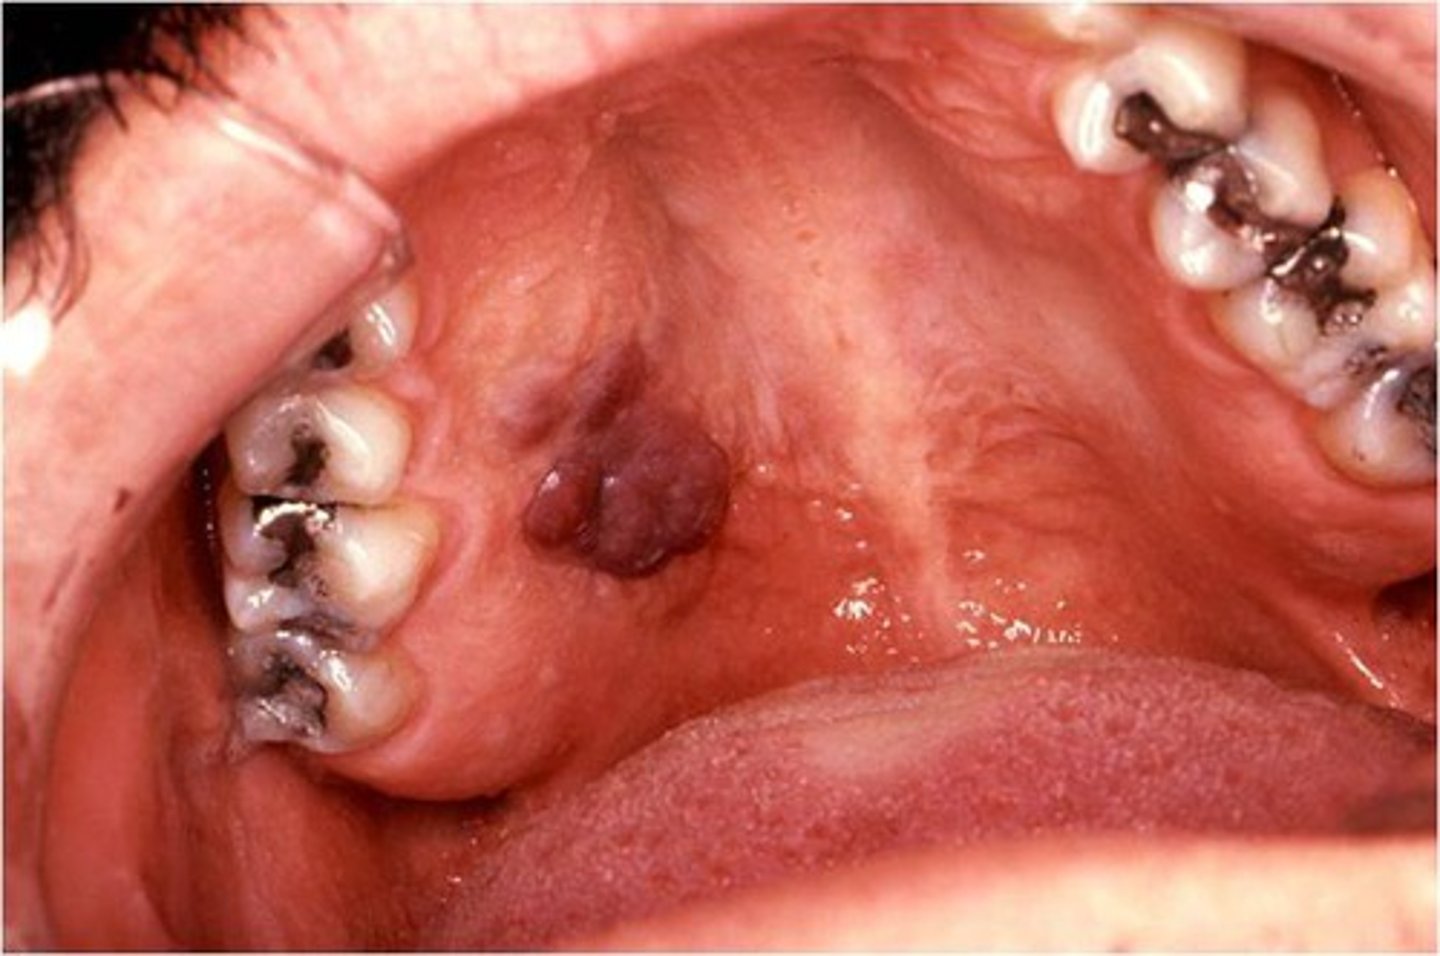

kaposi sarcoma

deep purple, nontender lesions may be raised or flat

HHV 8

<p>deep purple, nontender lesions may be raised or flat</p><p>HHV 8</p>